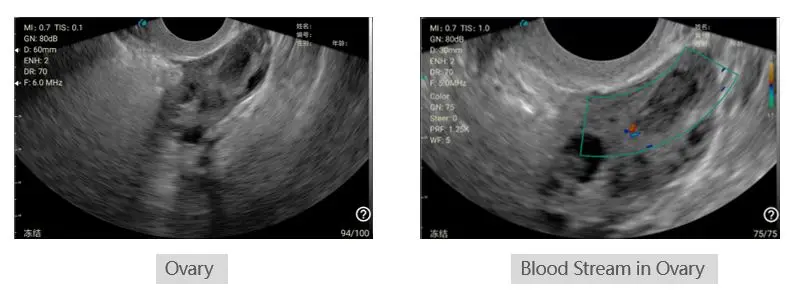

Convex probe Portable wireless Ultrasound Scanner Machine for Gynecology and Obstetrics